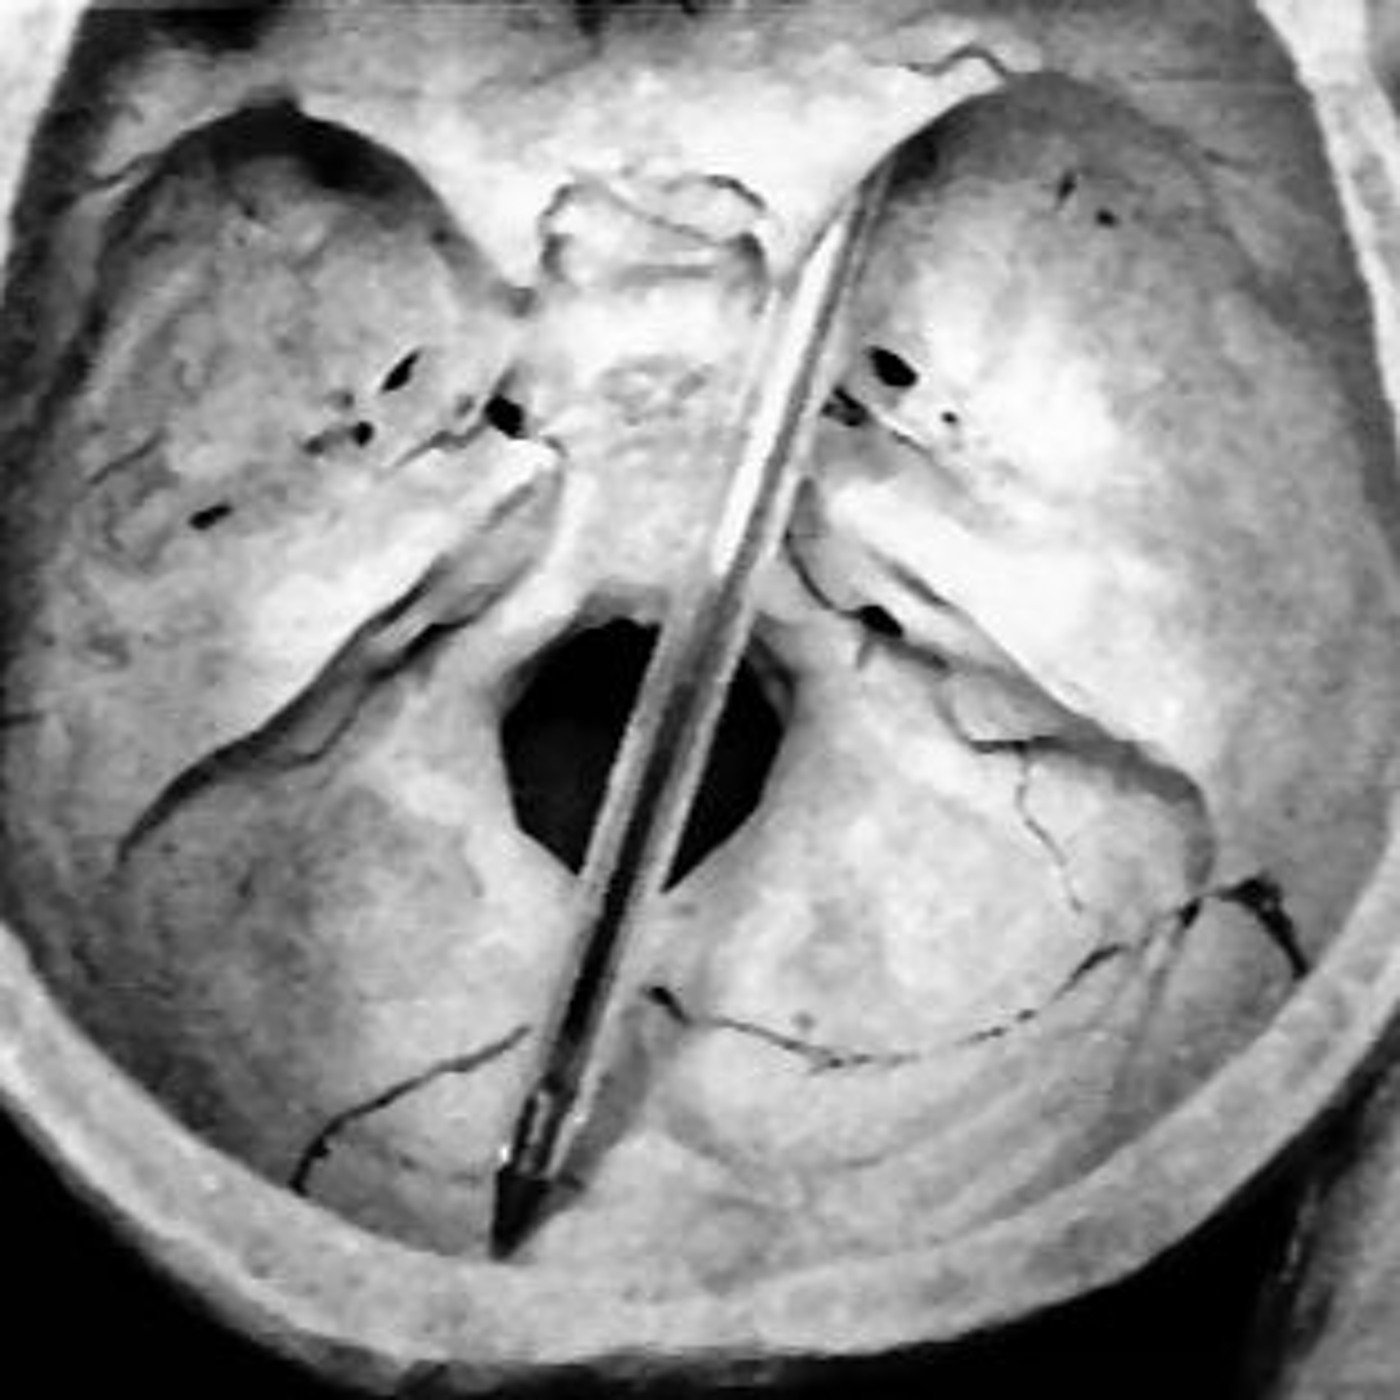

Wanneer in Leiden een 53-jarige vrouw thuis dood wordt aangetroffen, is er op het eerste gezicht niets bijzonders te merken aan het overlijden. Bij de autopsie echter treffen de onderzoekers een intacte zwarte balpen aan in de schedel van de vrouw. Hoe die daar terecht is gekomen? Daar zijn de meningen over verdeeld. Hier is aflevering 51!